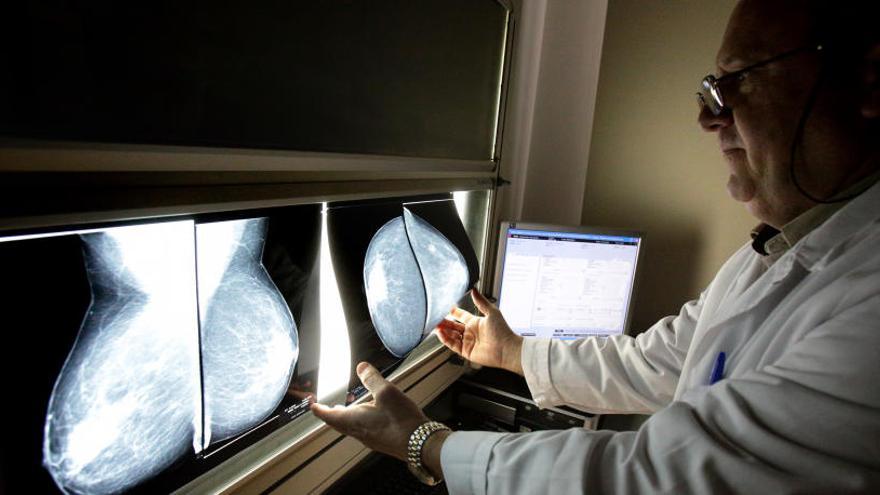

Así, el Hospital de Sant Joan recibirá un PET-TAC; los hospitales de Alcoy, Orihuela, General de Alicante (2) y La Vila contarán con un mamógrafo. Además, el Hospital de Sant Joan recibirá otro aparato de Resonancia Magnética; el General de Elche y el Hospital de Orihuela recibirán sendos TAC.